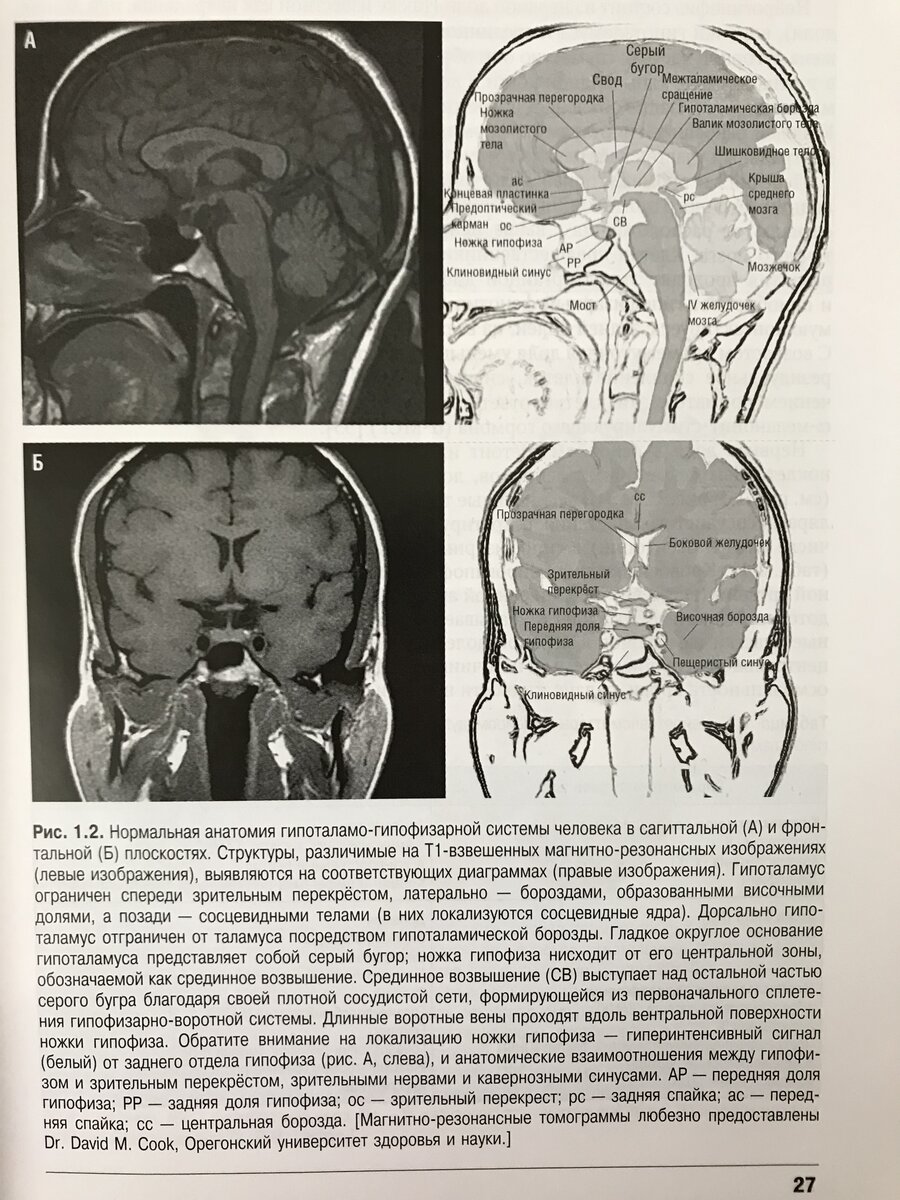

Методом выбора визуализации гипофиза и гипоталамуса, а также методом выбора топической диагностики новообразований гипоталамо-гипофизарной области является МРТ .